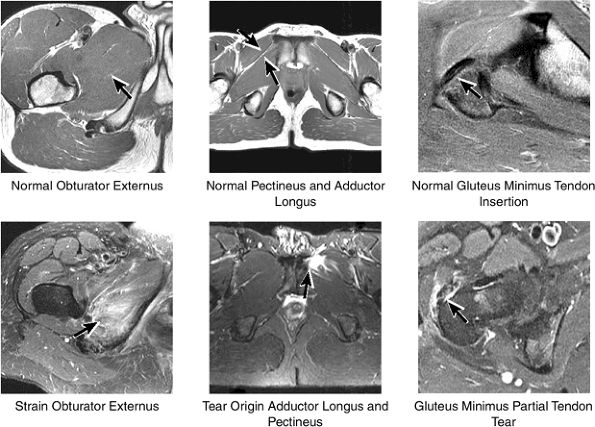

FIGURE 3.29 ● Normal axial anatomy of the hip. (A, B) At this level, the sciatic nerve can be seen exiting the sciatic foramen, deep to the piriformis muscle. Asymmetric enlargement of the piriformis muscle or masses in this region can cause impingement of the sciatic nerve, the so-called piriformis syndrome. (C, D) At this level the transition from the acetabular roof to the top of the femoral head is visualized. The thin arc of dark signal along the lateral margin of the acetabular roof represents the superior margin of the labrum. High signal in the superior labrum can be identified as a labral tear, and accompanying paralabral cysts are commonly identified extending superficial to the labrum. (E, F) The anterior labrum and the posterior labrum on axial images are identified as dark-signal triangles at the lateral margin of the acetabuli. Labral tears present as linear or irregular fluid signal extending through the substance of the labrum, or as expansion of the labrum by fluid signal extending to the surface of the labrum. Fluid signal interposed between the labrum and the acetabulum at the labral attachment indicates labral detachment.(G, H) Tendinosis of the gluteus medius and minimus insertions on the greater trochanter is visualized as thickening and increased signal of the tendons. Trochanteric bursitis can be identified either superficial or deep to the gluteus medius and minimus insertions. (I, J) A fluid collection anteromedial or anterolateral (or both) to the iliopsoas tendon is compatible with iliopsoas bursitis. Occasionally, iliopsoas bursitis may be present adjacent to an anterior labral tear, in which case it may be difficult to distinguish from a paralabral cyst. (K, L) The common hamstring origin on the ischium comprises the biceps femoris and semitendinosus tendons. The common hamstring tendon is a frequent site for tendinosis or partial tears, and the pathology is commonly symmetric.